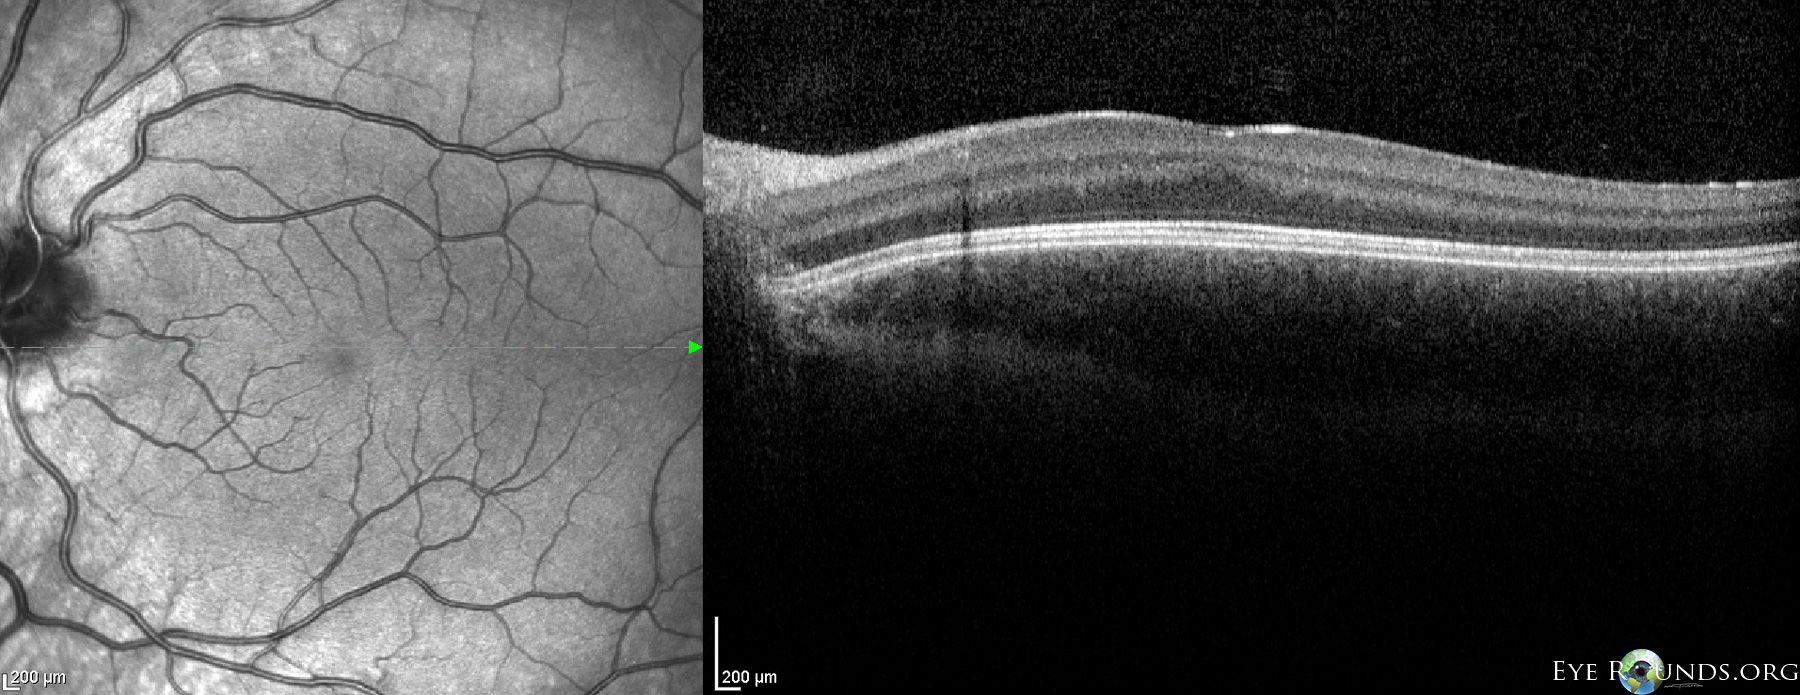

This 7-year-old girl presented with decreased vision and nystagmus and was diagnosed with oculocutaneous albinism (OCA).

OCA is typically inherited in an autosomal recessive fashion and is characterized by decreased melanin and subnormal vision since birth. Findings on exam include hypopigmentation of the skin, hair, and irides with diffuse iris transillumination defects on retroillumination, as seen in the photograph. Decreased acuity can be attributed to foveal hypoplasia which is apparent as an abnormally small or absent foveal depression as seen in this optical coherence tomography (OCT) render. Albinism can also be limited solely to the eyes in ocular albinism which most commonly has X-linked recessive inheritance.